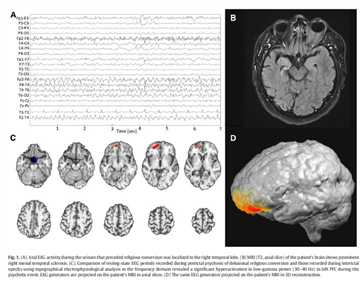

• 前额叶腹侧皮质病变带来的30~40赫兹的伽马波会让人产生宗教狂热[4]

技术分享图片